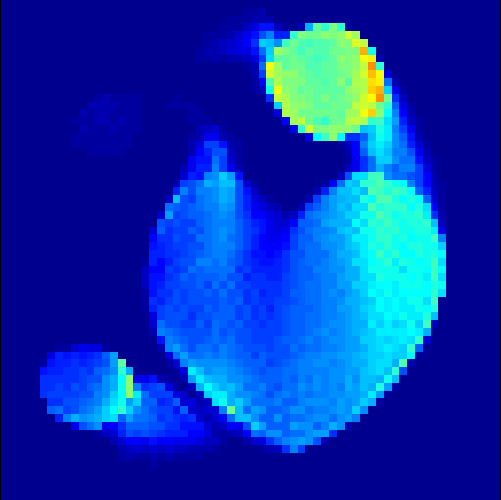

5.2 Monte Carlo Simulation

In order to test the behaviour of the proposed method in a more realistic, random-based test case, we performed a Monte Carlo simulation for dynamic SPECT imaging. First, we created a simple image phantom consisting of an outer and two inner circles which represents the structure of the region of interest (see figure 8(a)). Within those regions we assumed concentration curves over a time period of 90 time steps as displayed in figure 8(b). Based on the tracer intensity in an image frame at each time step, we created a variable number of random decay events (where the number is proportional to the average concentration in one pixel in the whole image frame per time step) with a probability proportional to the concentration in every subregion. They are detected by a virtual double head gamma camera rotating around the patient by 46 degrees per time step, which consists of 374 detector bins. Every simulated decay event is projected onto the scanner and counted by the corresponding detector bin.

In two different tests we fixed the number of events counted by the detector equal to (resp. ) times the average concentration in one pixel. The resulting sinogram images of the accumulated counts in each bin are shown in figure 9.

Based on the sinogram data we applied the proposed algorithm in order to reconstruct the original image sequence. The results for both test cases are shown in figure 10.

As one can see, the method is able to reconstruct the regions properly, even in case of a low count number. Within a number of iterations (average of 100 outer and 10000 inner iterations), the algorithm presents a reasonable reconstruction of the region of interest and the corresponding regional tracer concentration curves. Here, the parameters were not optimized as in the case of the synthesized data sets in the previous section, but kept fixed as , and . With futher optimized parameter values one could possibly provide even better results.